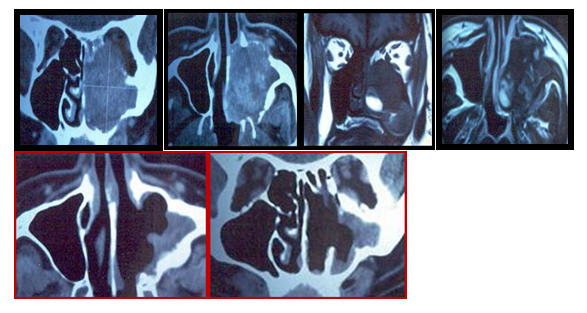

We analyzed the clinical histories of all adult patients who underwent an endonasal approach with endoscopes, for having hemangiomas of the nasal cavity and paranasal sinuses in the Italian Hospital of Buenos Aires, between June 2006 and December 2016. We excluded patients with hemangiomas who were less than 18 years old, with small tumors (less than 2 cm), vascular malformations, and those who underwent surgical procedures performed externally. All were studied by nasal endoscopy, computed tomography and magnetic resonance with contrast. The surgeries were performed under general anesthesia, with endoscopes of 0° and 30°, conventional surgical instruments were used for rhinosinusal endoscopic surgery. By endonasal approach a maxillary antrostomy, ethmoidectomy, and a middle turbinate resection were performed, and the tumor was resected. In another patient, the sphenopalatine artery was also cauterized, and a sphenoidotomy was performed, and in the remaining patient, the tumor of the nasal cavity was directly resected. The follow-up was performed by nasal endoscopy, computed tomography and/or magnetic resonance with contrast.

Four patients were treated for nasal cavity (1/4) and paranasal sinuses (3/4) hemangiomas through an endonasal approach with endoscopes between June 2006 and December 2016, at the Hospital Italiano de Buenos Aires. Three were men and one woman, the youngest was 36 and the oldest 65 years, the average age was 46.6 years. The main reason for consultation was unilateral (1/3), bilateral (1/3) nasal obstruction, and epistaxis (1/3). One patient also had epiphora, and proptosis was detected in two. In one of the patients, the hemangioma was a finding in a tomography requested to complete the evaluation for sleep apnea. Two tumors were located mainly in the maxillary sinus (one right and one left), displaced the eye and one had involved of the both nostrils and it spread to rhinopharynx. Another was located in the posterior ethmoid and another in the nasal cavity. In the 2 patients with giant tumors located in the maxillary sinus, endonasal biopsies were performed. One of the patients required a nasal tamponade due to significant bleeding.